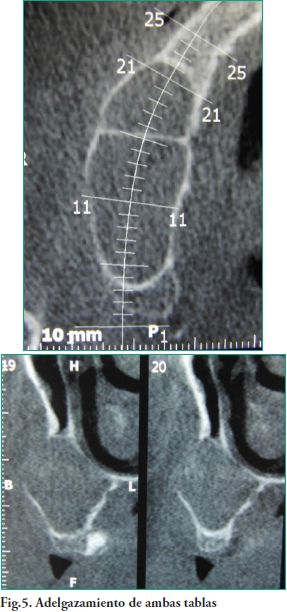

A efectos del diagnóstico y plan de tratamiento se indica una Tomografía Computada (TC), examen realizado a través de adquisición de haz cónico único de rayos X, donde se corroboran las medidas de la lesión de 40.2 mm. en sentido ántero posterior por 30.1mm en sentido vertical. En todos los cortes tomográficos se observa que el seno maxilar derecho está ocupado por una lesión, con un tabicamiento a la altura del 13, que no deforma la pared nasal del seno maxilar (Figs. 4, 5).

El Mucocele de seno maxilar clínicamente puede presentarse con abultamiento de la mejilla, diplopía y problemas dentarios, aunque típicamente sin dolor (3). En las fases tempranas el diagnóstico es casual, casi exclusivamente al realizar una Tomografía Computarizada de senos paranasales (12). La Tomografía tipo ConeBean (T.C.B.) describe a los mucoceles como una masa homogénea, hipodensa e isodensa como se ve en una T.C. de cerebro (13) y típicamente muestra un contorno redondeado a nivel óseo (13-16) no siendo necesario la inyección de un medio de contraste para su diagnóstico. El detalle óseo es una ventaja añadida de la T.C.B. (15-17) ya que un seno maxilar radio opaco, sin erosión ósea, invita al diagnóstico de sinusitis, pólipos y quistes de retención antrales (18).El Mucocele de seno maxilar típico, opacifica por completo el antro y expande la cavidad sinusal (10). En la fase temprana no se puede diferenciar un seno con obstrucción transitoria lleno de moco, de un seno similar obstruido, con formación posterior de un mucocele. El diagnóstico definitivo sólo puede establecerse cuando existe expansión sinusal (12, 19). Con expansión y destrucción ósea, el diagnóstico diferencial incluye las condiciones malignas como el carcinoma adenoide quístico, plasmocitoma, rabdomiosarcoma, linfoma, schwannoma y tumores de origen dental (14). Tradicionalmente la erosión ósea no se asocia con el mucocoele de seno maxilar. En nuestro paciente había producido el adelgazamiento de las pared posterior y medial del antro maxilar tal cual lo describe la literatura consultada (4) con una pérdida ósea a la altura de la zona de la pieza 16. Sostenemos que un gran mucocele puede causar erosión ósea, pero la naturaleza homogénea de la lesión maxilar junto con la conservación de los planos mucosos adyacentes al hueso erosionado, revela la naturaleza benigna de la enfermedad. Histológicamente, el mucocele de seno maxilar está limitado por una cápsula epitelio-conectiva, constituida por mucosa respiratoria normal (epitelio seudoestratificado cilíndrico ciliado), el corion subyacente presenta fibrosis e inflamación crónica. Es raro encontrar epitelio escamoso metaplásico, siendo la mucosa respiratoria ciliada el revestimiento más frecuente (19-21). Para explicar los mecanismos responsables de la formación y crecimiento del mucocele, se han propuesto muchas teorías incluyendo la degeneración quística de una glándula seromucosa, aunque los análisis histopatológicos y moleculares realizados por Lund et al. (22, 23), analizan un proceso dinámico de resorción ósea, en el que la inflamación interviene mediante las citoquinas que actúan entre el hueso y epitelio, con la producción de prostaglandinas, las cuales desempeñan un papel crucial en su desarrollo junto con la obstrucción sinusal. A su vez los Mucoceles pueden ser el resultado de un trauma facial o cirugía previa pudiendo producir áreas compartimentadas como presentaba la paciente de referencia (8). En el caso que nos ocupa no se tenía certeza del diagnóstico, por lo que inicialmente se planificó la biopsia incisional y cuando se hizo el abordaje y se certificó la benignidad clínica de la lesión, se procedió a la exéresis total de la misma, sin contrabertura nasal a nivel del meato inferior como se indica para este tipo de tratamiento y por ese motivo se indicó gotas nasales para mantener permeable el ostium. Como complemento del tratamiento quirúrgico se prescribió Amoxicilina en dosis de 500 mg. cada 8 hrs. por un período no menor a 7 días, y como analgésico Ibuprofeno en dosis de 400 mg. cada 6 hrs. por un tiempo mínimo de 48 horas. La evolución fue favorable a corto plazo, con un seguimiento de dos meses.